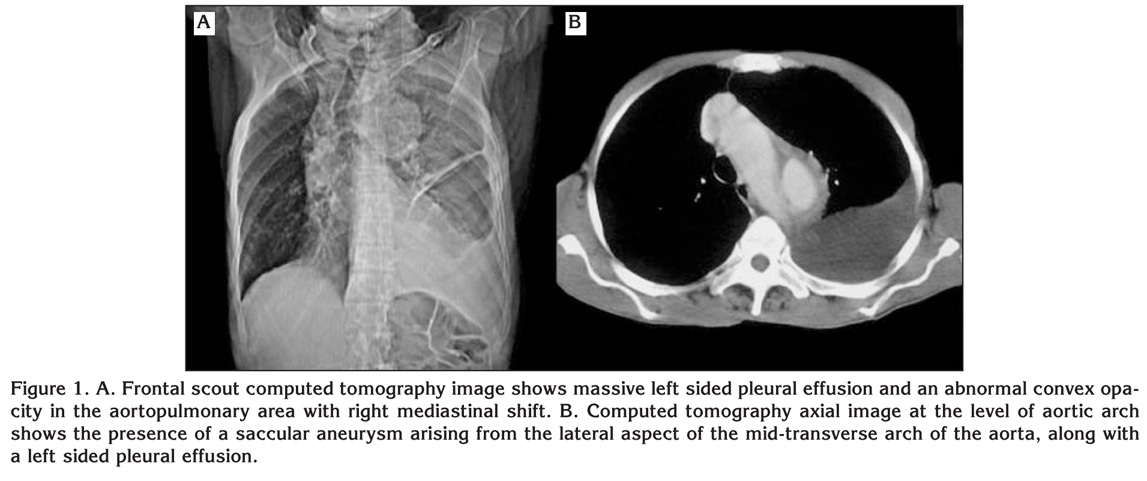

Biochemical analysis demonstrated normal cardiac enzyme level and presence of normochromic and normocytic anemia with hemoglobin of 10 g/100 mL. Chest X-ray was done, which shows massive left sided effusion and an abnormal convex opacity in the aortopulmonary area with right mediastinal shift (Figure 1A). The patient was put in a propped up bed with moist O2 and IV fluid with cephalosporin and deriphylline was started.

Figure 1

Computed tomography (CT) scan revealed a saccular aneurysm arising from the lateral aspect of the mid-transverse arch of the aorta, along with a dissecting descending aortic aneurysm (Figure 1, 2). An intimal flap was seen separating the true lumina and false lumina, which communicated with the left pleural space. The presence of hyperdense fluid in the left pleural space signified a leaking aortic aneurysm. Magnetic resonance imaging (MRI) was done which confirm the nature of lesion (Figure 3).